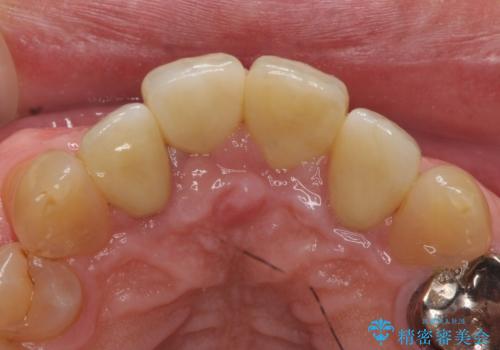

再根管治療後、オールセラミッククラウンによる補綴を行いました。

今回用いたオールセラミッククラウンは、ジルコニアフレームという白い素材の上にセラミックを盛っているため審美性が非常に高いのが特徴です。

またジルコニアは人工ダイヤモンドの材料にも使われているほど高い強度を持っており、そのためオールセラミッククラウンは審美性だけでなく、奥歯やブリッジの補綴も可能とするクラウンです。